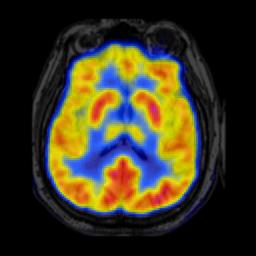

In image fusion, images obtained from different sensors are fused to generate a single image with enhanced information. In recent years, state-of-the-art methods have adopted Convolution Neural Networks (CNNs) to encode meaningful features for image fusion. Specifically, CNN-based methods perform image fusion by fusing local features. However, they do not consider long-range dependencies that are present in the image. Transformer-based models are designed to overcome this by modeling the long-range dependencies with the help of self-attention mechanism. This motivates us to propose a novel Image Fusion Transformer (IFT) where we develop a transformer-based multi-scale fusion strategy that attends to both local and long-range information (or global context). The proposed method follows a two-stage training approach. In the first stage, we train an auto-encoder to extract deep features at multiple scales. In the second stage, multi-scale features are fused using a Spatio-Transformer (ST) fusion strategy. The ST fusion blocks are comprised of a CNN and a transformer branch which capture local and long-range features, respectively. Extensive experiments on multiple benchmark datasets show that the proposed method performs better than many competitive fusion algorithms. Furthermore, we show the effectiveness of the proposed ST fusion strategy with an ablation analysis. The source code is available at: https://github.com/Vibashan/Image-Fusion-Transformer.